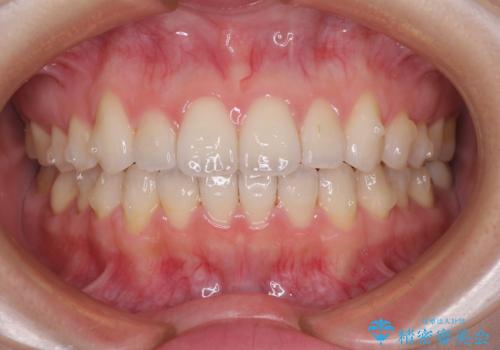

- 矯正治療の後戻りを気にして来院された患者様です。

後戻りは軽微でしたが、舌突出癖が認められ、初診時には上下前歯に舌がはまるスペースができていました。

舌突出癖の改善を行いながら、インビザライン・ライトにより矯正治療を行うこととしました。

舌突出癖の改善により上下前歯が接触するようになり、前歯でものを咬みきる必要のある食事がスムーズに行えるようになりました。